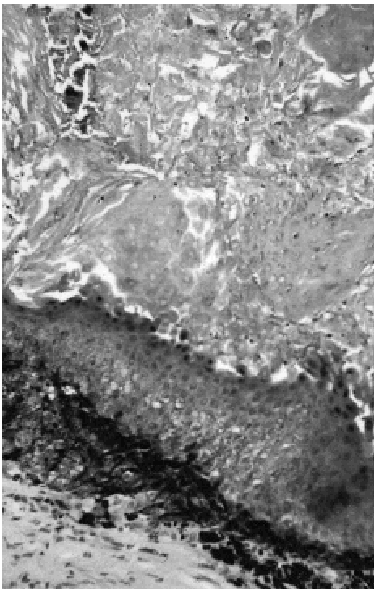

Bajo la sospecha de quiste epidermoide se procedió a la extirpación completa de la lesión bajo anestesia local. El examen macroscópico de la pieza evidenciaba que se trataba de una neoformación encapsulada de 1,8 x 1,6 x 1,5 cm, con tonalidades negruzcas en alguna zona. El estudio histopatológico mostró un pilomatricoma en el que se apreciaba gran cantidad de pigmento melánico en el interior, tanto de las células basófilas como de las fantasmas, así como en macrófagos del parénquima (fig. 1). Además se podía apreciar la presencia de algunos melanocitos dendríticos intercalados entre las células del tumor (fig. 2).

Fig. 2.--Pigmentación intensa alrededor y entre células basófilas y fantasma, con presencia de algunos melanocitos dendríticos (S-100 x 400).